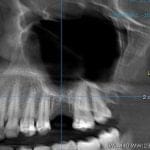

Vilični ili maksilarni sinusi su parne šupljine u telu gornje vilice, koji svojom pozicijom mogu da budu u bliskom kontaktu sa položajem korenova gornjih bočnih zuba. Njihova veličina je individualna i genetski definisana. Mogu da budu manjeg promera i da se ne nalaze u projekciji korenova zuba gornje vilice, a s druge strane mogu da budu izuzetno voluminozni pa da se protežu od korenova prekutnjaka, a ponekad i od očnjaka, sve do poslednjeg kutnjaka u vilici.

Dijagnoza sinuzitisa se postavlja detaljnom anamnezom, kliničkim pregledom, kao i analizom rentgenskih snimaka (snimak paranazalnih šupljina, OPT snimak kao i 3D snimak).